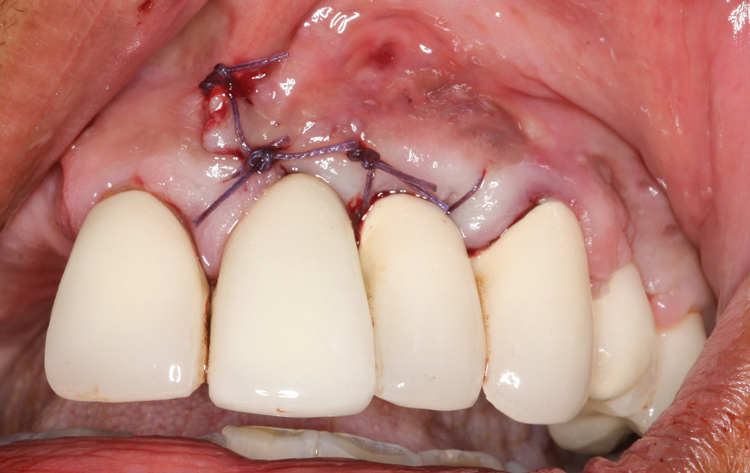

There are many grafting materials available today, including allografts (from a human source), xenografts (from another species), and alloplasts (from synthetic materials).23 Following debridement and sterilization of the apical lesion, the site was grafted with a mineralized cortical/cancellous bone allograft material (Newport Biologics Mineralized Cortico/Cancellous Allograft Blend, Glidewell Direct [alternatively: OSSIF-I sem Mineralized Cortical/Cancellous Bone Allograft, Surgical Esthetics; enCore® 50/50 Cortical & Cancellous Allograft, Osteogenics]). The material was packed firmly around the entire implant body but not crushed (Figure 7). Next, a resorbable collagen membrane (Newport Biologics Resorbable Collagen Membrane 3-4, Glidewell Direct [alternatively: Bio-Gide®, Geistlich Biomaterials; BioMend®, Zimmer Biomet]) was trimmed to extend approximately 2-mm beyond the borders of the defect and then passively positioned to serve as a barrier against epithelial growth during the healing and remodeling phase (Figure 8). A sling suture technique using polyglactin 910 suture was then used to reposition the envelope reflection (Figure 9 through Figure 11). Polyglactin 910 suture is a smooth, synthetic, absorbable, braided suture made of polyglycolic acid that is broken down over time by hydrolysis. This suture material reduces the inflammatory response that can be observed with other suture materials.

(9.) A sling suture technique was used to reposition and secure the reflected tissue.

Figure 9

(10.) A sling suture technique was used to reposition and secure the reflected tissue.

Figure 10

(11.) A sling suture technique was used to reposition and secure the reflected tissue.

Figure 11